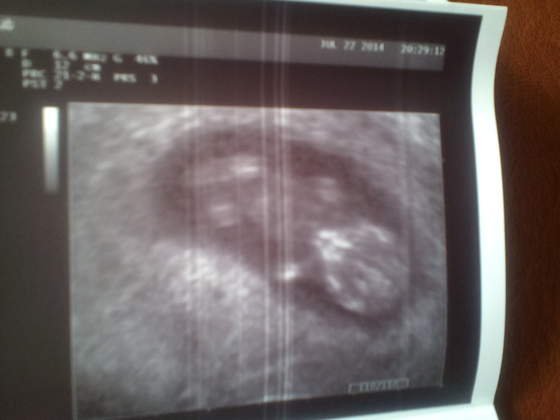

Tarantina, Adaś w 11 tygodniu :) Jakie to było piękne :)

• IMG_20140723_161357.jpg

IMG_20140723_161357.jpg

16,3 KB · Wyświetleń: 75